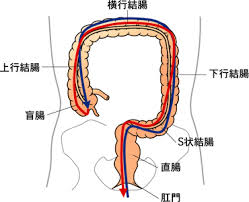

大腸の長さはどのくらいあるかご存じでしょうか?

約1.5m。

おおよそ身長くらいあると言われています。

それは、長い腸をアコーディオンのように縮めて80㎝くらいにして奥まで挿入します。

例えるとズボンのゴムを通すような感じ?たぐってたぐって入れていきます。

でも「腸が硬い」と上手くたぐれないから、挿入に時間がかかり苦労します。普通の人より検査時間がかかるため、順番を後のほうにしないと他の患者さんを長い時間待たせてしまいます。

腸が硬いとなぜ便秘になりやすいかというと・・・

うんちは腸が伸びたり縮んだりしながら肛門の方へ押し出されていきます。

しかし、腸が硬いとこの押し出し運動が上手く行われません。

古く硬くなったホースを思い浮かべてもらえばわかりやすいかな?